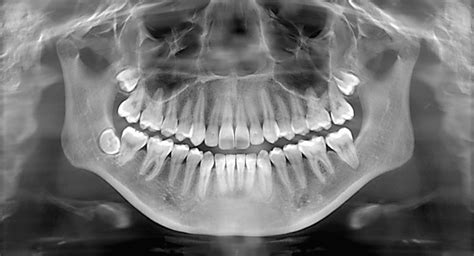

X-rays

In some cases, your dentist may require X-rays to assess the condition of the tooth and surrounding structures. X-rays can help identify any underlying issues that may affect the bonding process. The cost of dental X-rays ranges from $25 to $200, depending on the type of X-rays required and the dental office.

2. X-rays and Diagnostic Tests

X-rays and diagnostic tests are often necessary to determine the extent of the chip and to create an accurate treatment plan. These tests may include dental imaging, such as digital X-rays or 3D scans, which provide detailed images of the affected tooth and surrounding structures. The cost of these tests can vary depending on the dental clinic and the number of scans required.